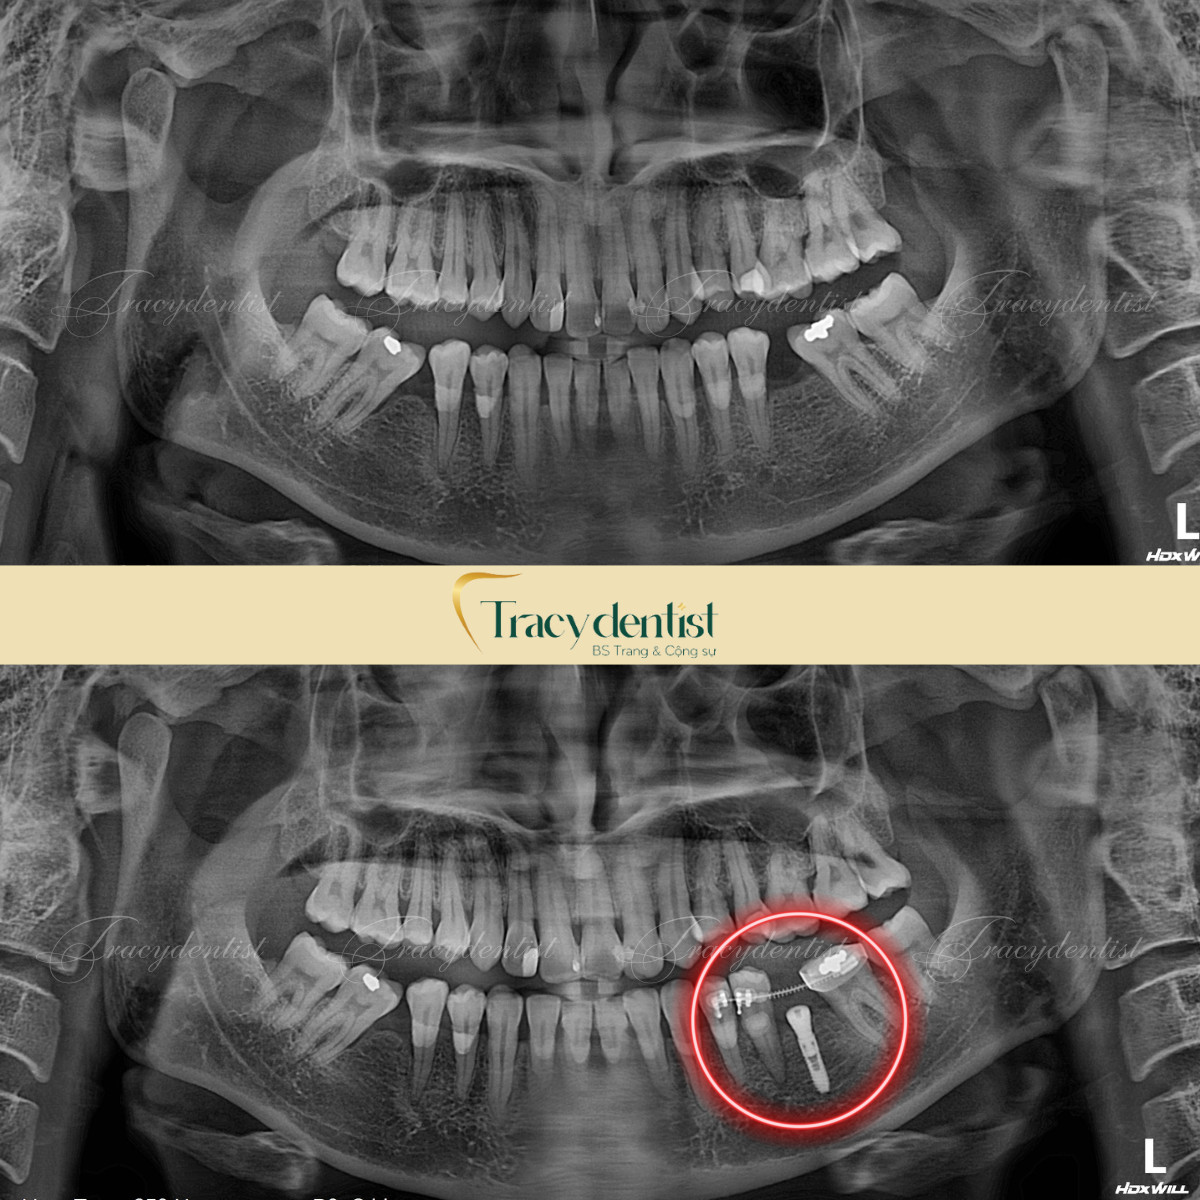

Chụp CT để kiểm tra tình trạng xương, răng trước khi điều trị

Trước khi tiến hành phẫu thuật trồng răng implant, bệnh nhân sẽ được thực hiện chụp CT và kiểm tra để bác sĩ để đánh giá mức độ, tình trạng, và mật độ của xương, cũng như chiều cao xương và tình trạng răng, nhằm xác định khả năng thực hiện cấy ghép implant. Dựa trên kết quả hình ảnh từ CT, bác sĩ sẽ lập phác đồ điều trị, xác định vị trí đặt implant chính xác và lựa chọn kích thước trụ implant phù hợp nhất.

- Điều kiện để trồng răng là bệnh nhân phải có mật độ và sức khỏe xương đảm bảo.

- Kích thước xương hàm cần chuẩn, có mật độ xương ổn định, không quá giòn hay xốp

- Xương hàm có chiều rộng phù hợp với trụ implant mới có thể tích hợp chắc chắn vào mô xương và chịu được lực chắc chắn từ hoạt động ăn nhai, làm cho răng implant không bị đào thải ra ngoài và tồn tại vĩnh viễn trong môi trường miệng.

- Nếu như xương có chất lượng không đạt yêu cầu nhưng vẫn thực hiện việc trồng implant thì tỷ lệ đào thải sẽ rất cao. Lúc này bác sĩ sẽ thực hiện kỹ thuật ghép xương để hỗ trợ việc phục hình implant thành công.

Bên cạnh đó sau khi chụp CT xong bác sĩ sẽ vệ sinh khoang miệng và điều trị dứt điểm các bệnh lý răng miệng của bệnh nhân nếu có. Đây là quy trình bắt buộc cần phải thực hiện trước khi bước vào quá trình phục hình răng implant.